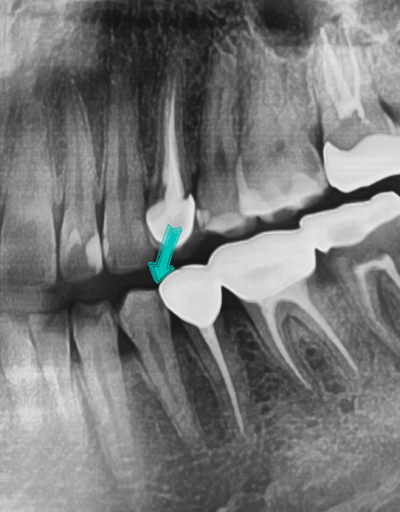

위 사진에서 화살표가 가리키는 까맣게 보이는 부분이 충치가 있는 것입니다. 치아와 옆치아 맞닿은 부분에 충치가 있는것인데요, 아마 그 부위에 음식물이 특히 많이 끼여서 충치가 생긴 것으로 생각됩니다.

겉으로 보이기에는 충치가 보이지 않았지만, 엑스레이 상에서 충치가 보이기 때문에 치료를 받아야한다고 말씀드렸고 이 부분에 맞는 치료는 인레이 임을 설명드렸습니다. 그러나 환자분이 아픈 치아만 치료 원하셨기 때문에 이 치아는 치료받지 않으셨습니다.